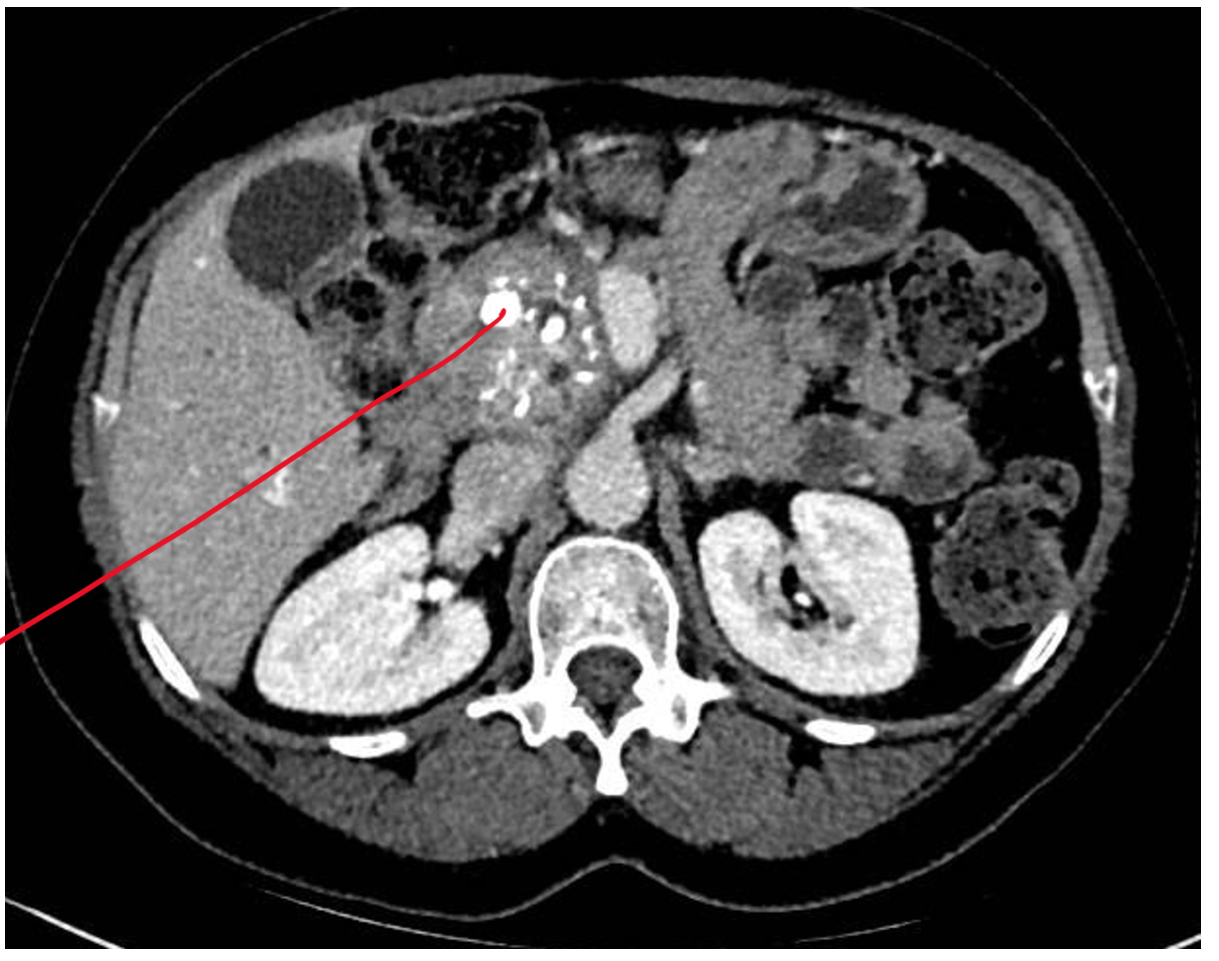

What is the definition of chronic pancreatitis and what are the signs you’d see on a CT scan for chronic pancreatitis

CT scan- would see calcium (white spots) deposit on head of pancreas